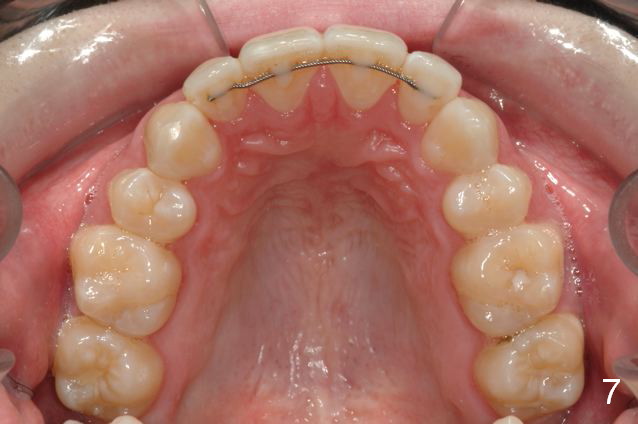

Initial information was obtained on 02/26/2014 (Fig.1-10). Anterior edge-to-edge and Posterior Open Bite (Fig.4 *): unfavorable differential Class III growth after orthodontics as a child.